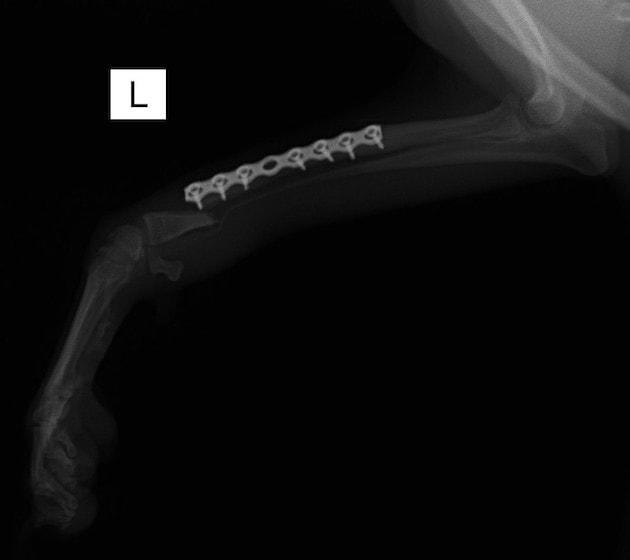

トイプードル 右遠位橈尺骨短斜骨折のALPSによる内固定

当院ではAdvanced Locking plate system(ALPS)と、Locking compression plate system(LCPS)という骨接合法で骨折症例の治療を行っています。

Advanced Locking Plate System

従来型のプレートのように広い面積で骨と接するプレートを用いて固定を行った場合、プレート下の骨はプレートとの接触面において血行が絶たれ壊死し、それがリモデリングされると骨密度が低下する。この骨密度の低下防ぐために、骨折部局所への血行を温存することの重要性が近年改めて認識されるようになってきている。Advaed Locking Plate System (ALPS)は従来型のプレートシステムの欠点を改良し、より使いやすく、より骨への血行を阻害しないようにというコンセプトで作られた。